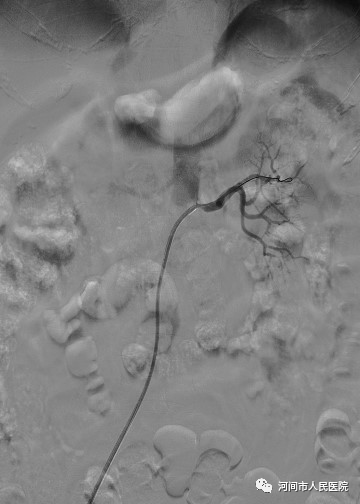

接受这例手术的患者,患严重高血压十余年,血压常年波动于160-200/90-120mmHg。更换多种降压药物依然效果不理想。心脑血管意外风险很大。入院后经彩超检查发现患者左侧肾动脉起始部严重狭窄。进一步查肾动脉CTA发现患者确实存在左侧肾动脉重度狭窄,并意外发现脾动脉动脉瘤。经神经内一科介入团队会诊后,给患者制定了一个最优治疗方案,介入治疗。于股动脉穿刺置管后由股动脉将导管置于左肾动脉起始部,经导管将一枚专用支架置于狭窄部位扩张,然后用导管选择进入脾动脉动脉瘤腔内,栓塞脾动脉动脉瘤。该治疗方案为微创手术,此治疗方法简便、快捷、患者无需行开腹手术,对身体基本无损伤。可同时行两个病变的治疗。

12月23日由孙东副主任医师为患者行左侧肾动脉支架置入术+脾动脉瘤栓塞术治疗。手术用时40分钟,术中成功置入左肾动脉支架后顺利将脾动脉动脉瘤栓塞,同时保持了脾动脉通畅,对患者脾脏无损伤。患者及家属非常满意。